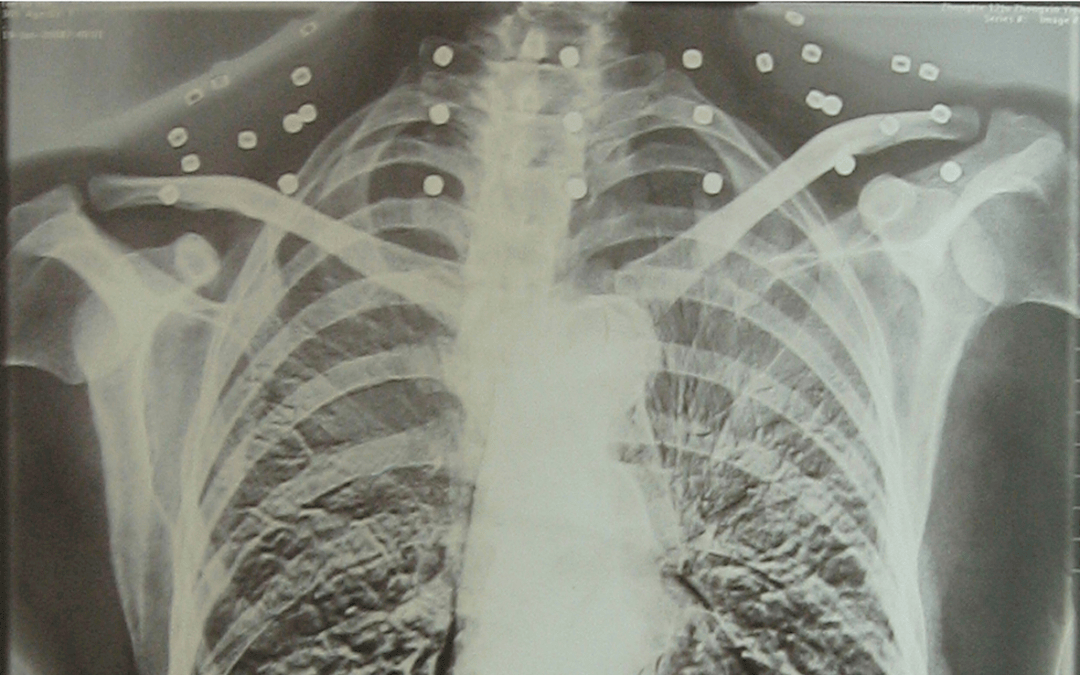

这张照片

是今年82岁的吴以先老人

拍摄的一张CT照

吴以先的颈部和腹部

共分布着33枚弹片

直到现在

皇冠信用怎么弄 他体内的弹片都没有取出

每到天气变化时

身体留有弹片的位置就有痛感

但吴以先不考虑取出弹片

在皇冠信用怎么弄 他看来

这是皇冠信用怎么弄 他与战友并肩作战的见证

是皇冠信用怎么弄 他的勋章